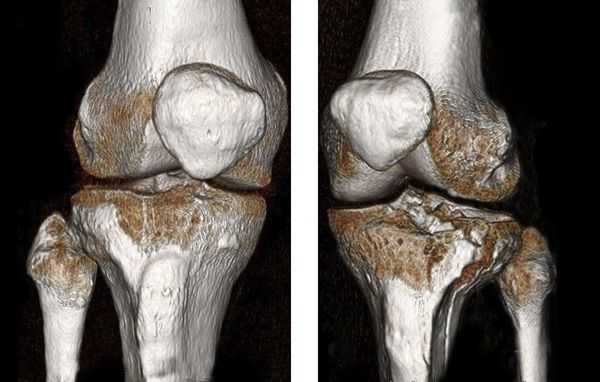

- Компьютерная томография правой голени.

Закрытый оскольчатый перелом внутренней лодыжки правой голени со смещением отломков. Закрытый перелом верхней трети малоберцовой кости правой голени. Повреждение дистального межберцового синдесмоза ( соединения большеберцовой и малоберцовой костей) . Подвывих стопы кнаружи (Maisonneuve-type fracture).